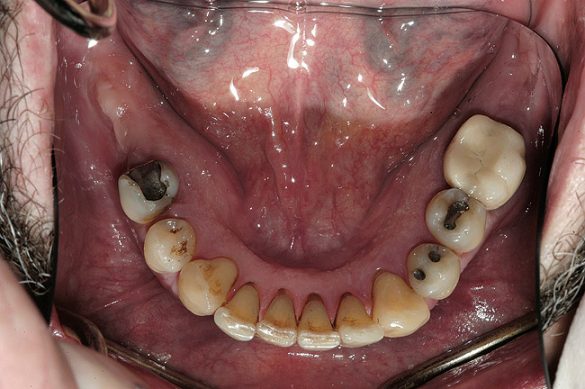

Obiective terapeutice

Consideraţiile privind managementul riscului şi planul de tratament au fost elaborate utilizându-se o abordare sistematică. Tratamentul ar fi redus riscul biomecanic prin eliminarea dinţilor compromişi structural (fig. 3,4), cu diminuarea concomitentă a riscului funcţional prin crearea unei ocluzii în armonie cu articulaţiile. În plus, tratamentul ar fi redus riscul parodontal prin îndepărtarea dinţilor irecuperabili, cu implicare parodontală, (fig. 5) şi ar fi îmbunătăţit estetica prin ridicarea cu 3mm a planului ocluzal pentru a minimiza expunerea gingivală şi a rădăcinilor.5-8

Examinarea a evidenţiat adâncimi de sondare generalizate cuprinse între 5-9mm, cu sângerare generalizată şi locaţii cu supuraţie. Combinaţia recesiunii cu adâncimile de sondare a generat o pierdere de ataşament generalizată cu valori între 8-12mm. Radiografiile au evidenţiat pierdere osoasă orizontală severă, defecte osoase verticale multiple şi aspectul unei posibile comunicări parodontale apicale. Aproximativ jumătate dintre dinţi prezentau mobilitate de clasa I, cu dinţii restanţi având o mobilitate de clasa a 2-a şi a 3-a. Toţi molarii manifestau cel puţin o invazie de furcaţie de gradul 1, cu multiple implicări de gradul 2 şi 3. Diagnosticul s-a stabilit a fi AAP tip IV, parodontită avansată.